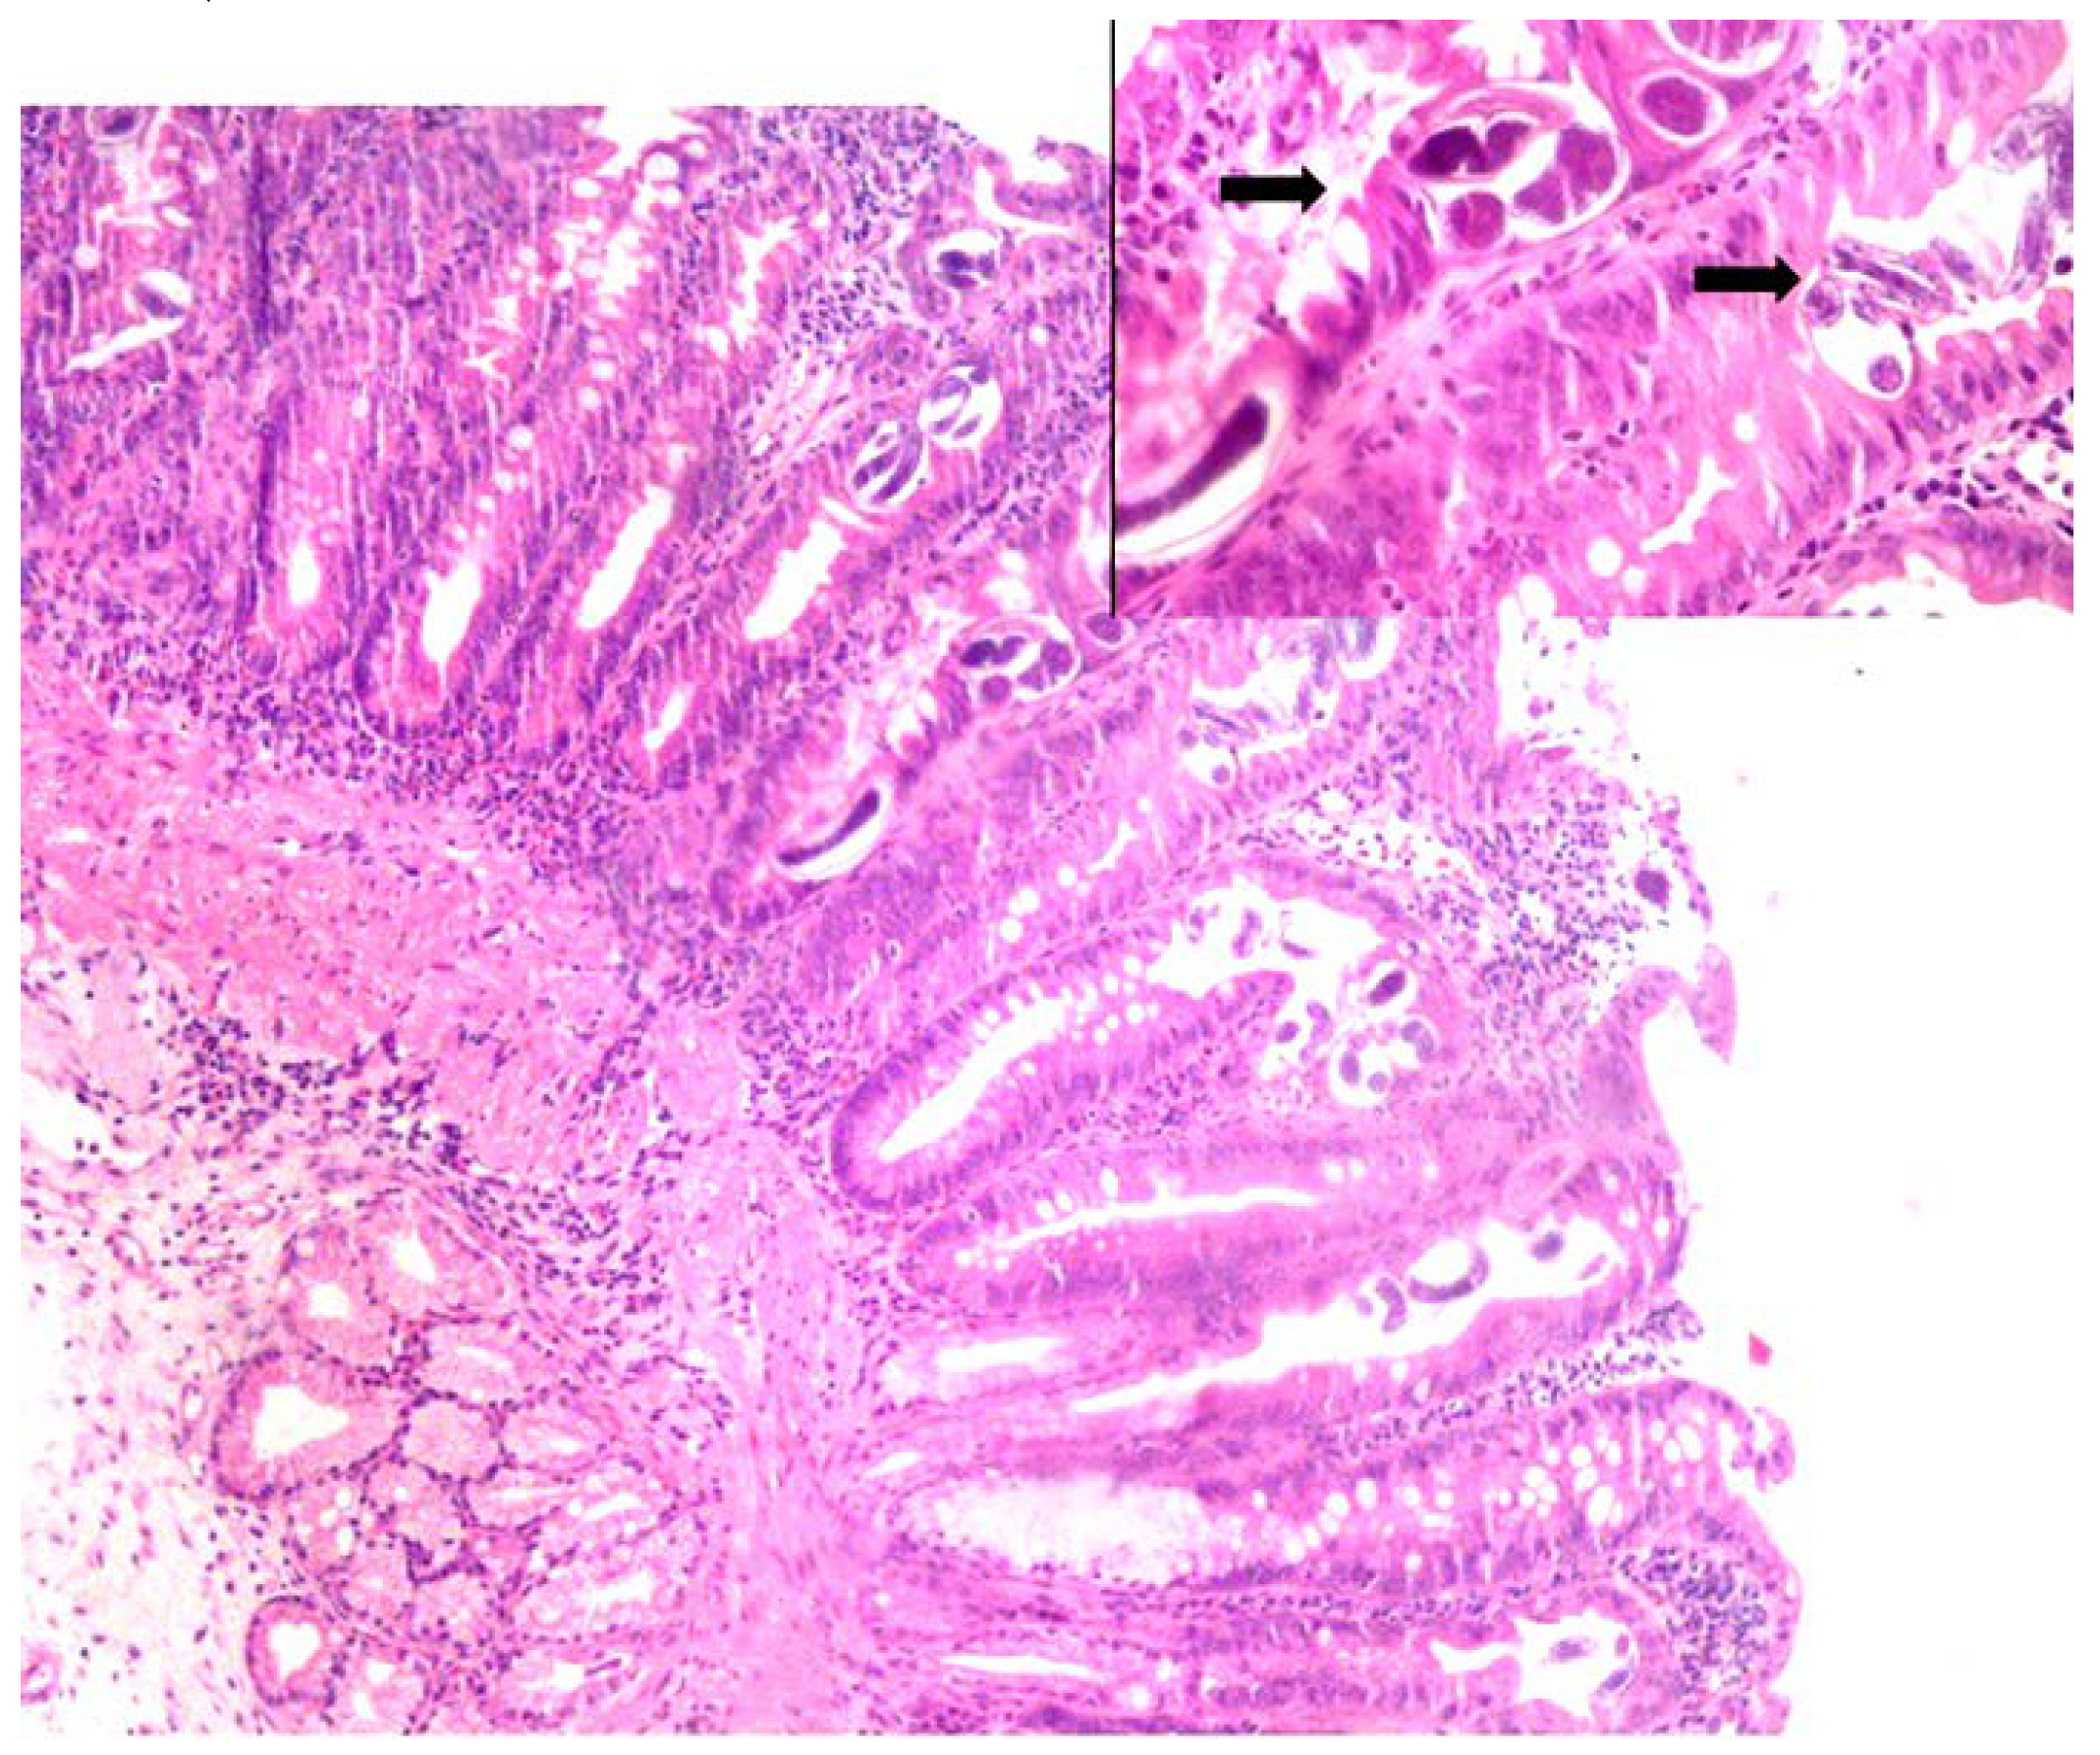

Figure 1.

The rhabditiform Strongyloides larva is seen in a stool sample of Case 1. Direct wet mount, magnification 50×.